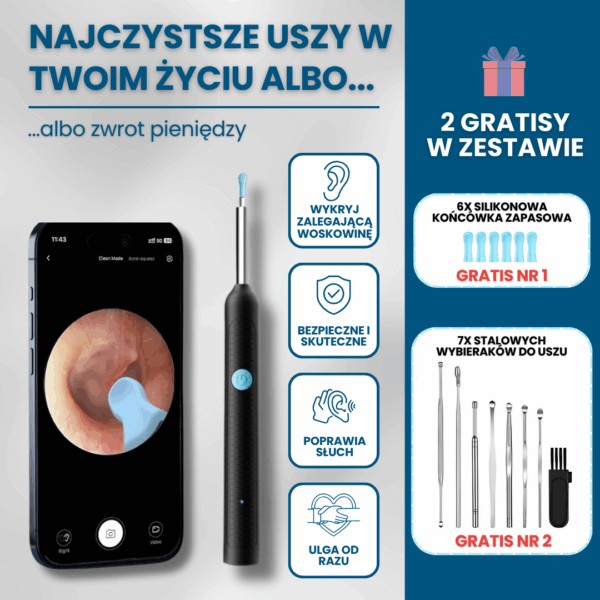

Pełna kontrola dzięki obrazowi HD 1080p — widzisz woskowinę i swobodnie ją usuwasz, zamiast ją wpychać. Miękkie silikonowe końcówki zamiast patyczków — precyzyjnie usuwa woskowinę, bez ryzyka zarysowań i dyskomfortu

Miękkie silikonowe końcówki zamiast patyczków — precyzyjnie usuwa woskowinę, bez ryzyka zarysowań i dyskomfortu Higieniczne i oszczędne — wielorazowe końcówki redukują odpady i koszty wymiennych patyczków.